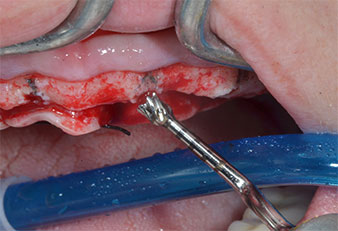

Para marcar las posiciones del implante y realizar la preparación piloto, se utilizó un inserto piezoeléctrico (Piezomed I1) con revestimiento de diamante y forma de llama (figura 3). Se tomaron precauciones para realizar movimientos hacia arriba y hacia abajo, con una potencia reducida, una irrigación completa y una baja presión (por debajo de 300 g). A continuación, se aplicó un inserto piloto (Piezomed I2A/I2P) para aumentar el diámetro inicial de 2 mm de los sitios de implante (figura 4), seguido de un inserto de 3 mm (Fig. 5).

En el caso que nos ocupa, no se utilizaron los insertos Z25P ni Z35P debido a la existencia de un hueso posterior relativamente blando, que se trató sin problemas con el I3A/I3P.

Debido al hueso relativamente duro (D2) existente en el sector anterior, los sitios de los implantes largos de 10 mm de las posiciones 11 y 21 se finalizaron con una fresa rotatoria de 4 mm de diámetro, en combinación con un contra-ángulo quirúrgico WS-75 L de W&H, el motor de implantes Implantmed de W&H y el módulo opcional Osstell ISQ de W&H. En cambio, debido a la existencia de hueso blando, los sitios posteriores se prepararon hasta un diámetro final de 3 mm utilizando el inserto Piezomed I3P. Por último, los implantes se colocaron a nivel crestal para su osteointegración durante tres meses (figuras 6-10). La prótesis existente se mantuvo sobre cuatro implantes provisionales (figura 8).